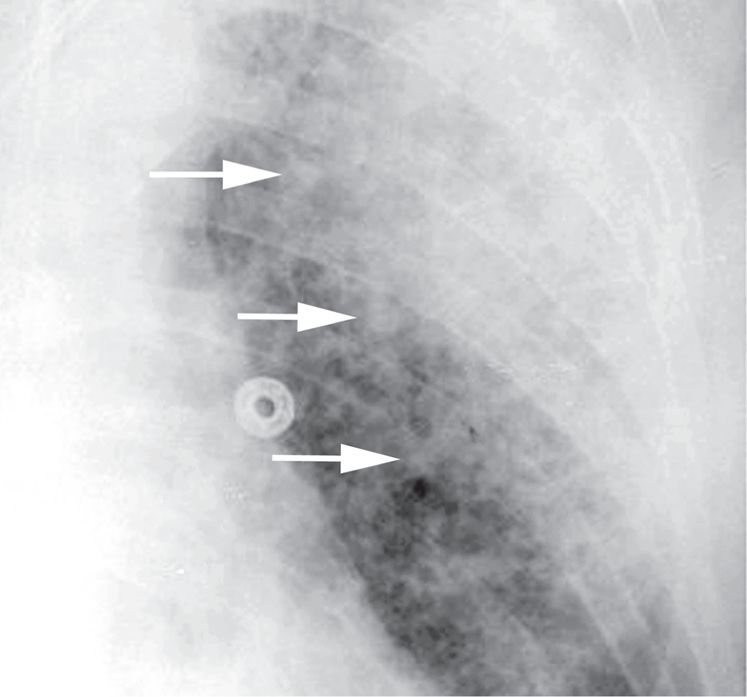

图2-5 实变:腺泡或气腔结节

胸部平片显示斑片状左上叶大叶性肺炎,致密实变影边缘可见直径小于1cm 的边界不清的结节样密度增高影( 箭头),代表气腔或腺泡结节;B. 双肺实变患者CT 显示( 层厚5mm),左肺下叶可见空气支气管征,并显示斑片状实变和毛玻璃样致密影, 右肺中叶、下叶可见气腔结节( 箭头)。这些结节边界不清,直径5 ~ 10mm,呈小叶中央分布